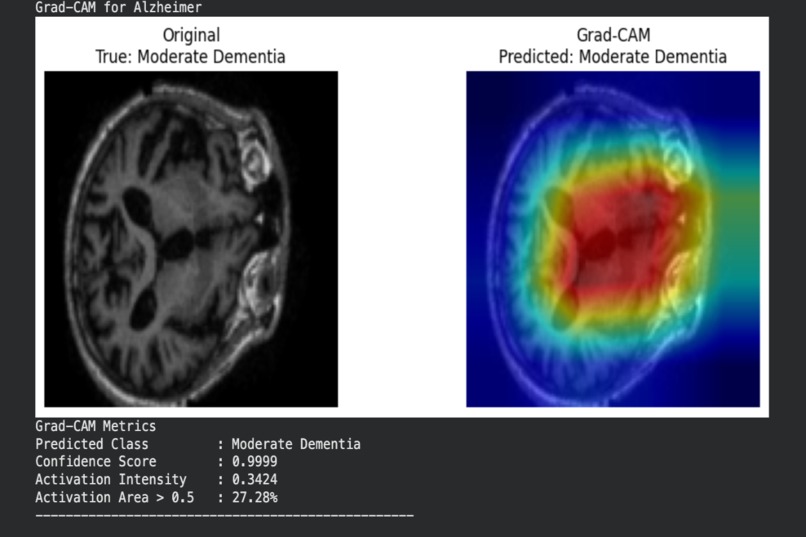

Alzheimer classification with Grad-CAM analysis

To improve trust and transparency, the system also generates Grad-CAM visualizations that highlight which regions of the brain influenced each prediction.

- Integrated Grad-CAM for visual explanations and added quantitative explainability metrics

- Ensuring model interpretability aligned with known neurological patterns

- Integrated explainability tools that provide clinically meaningful insights